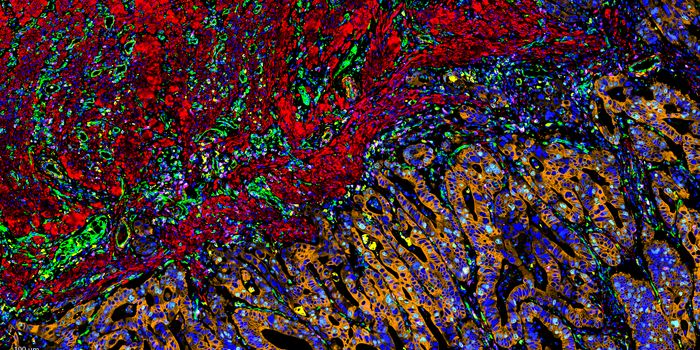

MAR 23, 2015VideosResearchers are using laser light to probe tiny samples of tumors to gauge their metabolic activity when dosed with a va ...